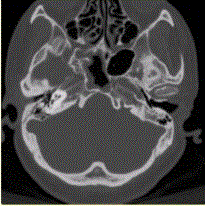

问题 患者男,20岁,外伤后右耳听力下降伴面瘫7d。临床检查,右耳传导性耳聋,发现脑脊液耳瘘。CT表现如下图。 临床拟诊为

选项 A.右侧颞骨骨折 B.右侧颞骨骨折,累及同侧外耳及面神经 C.右侧颞骨骨折,累及同侧中耳及面神经 D.右侧颞骨骨折,累及同侧内耳及面神经 E.右侧乳突骨折

答案 C